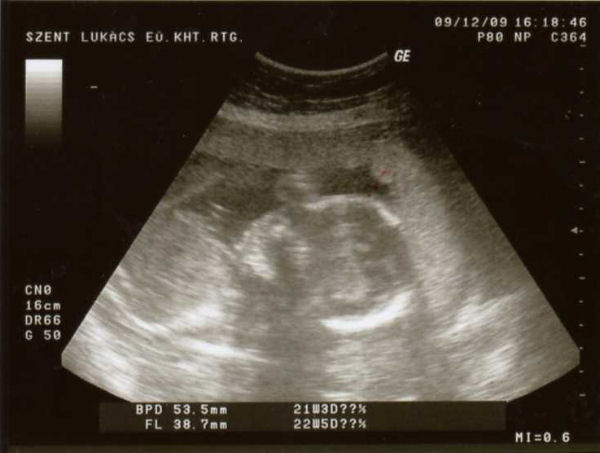

Nem látta a doki. Nem akrta megmutatni. Azt mondta, hogy valószínűleg kislány, mert azok ilyen szégyenlősek, de biztosra nem meri mondani. Azt mondta a méhlepényre, hogy még mehet feljebb, ha nem akkor császár lesz. Nem mondta, hogy ezzel most olyan komolyan kellene foglalkozni.

Na ilyenek vagyunk most. Elég szépen növögetünk, már lassan a képbe sem férünk el. :lol: